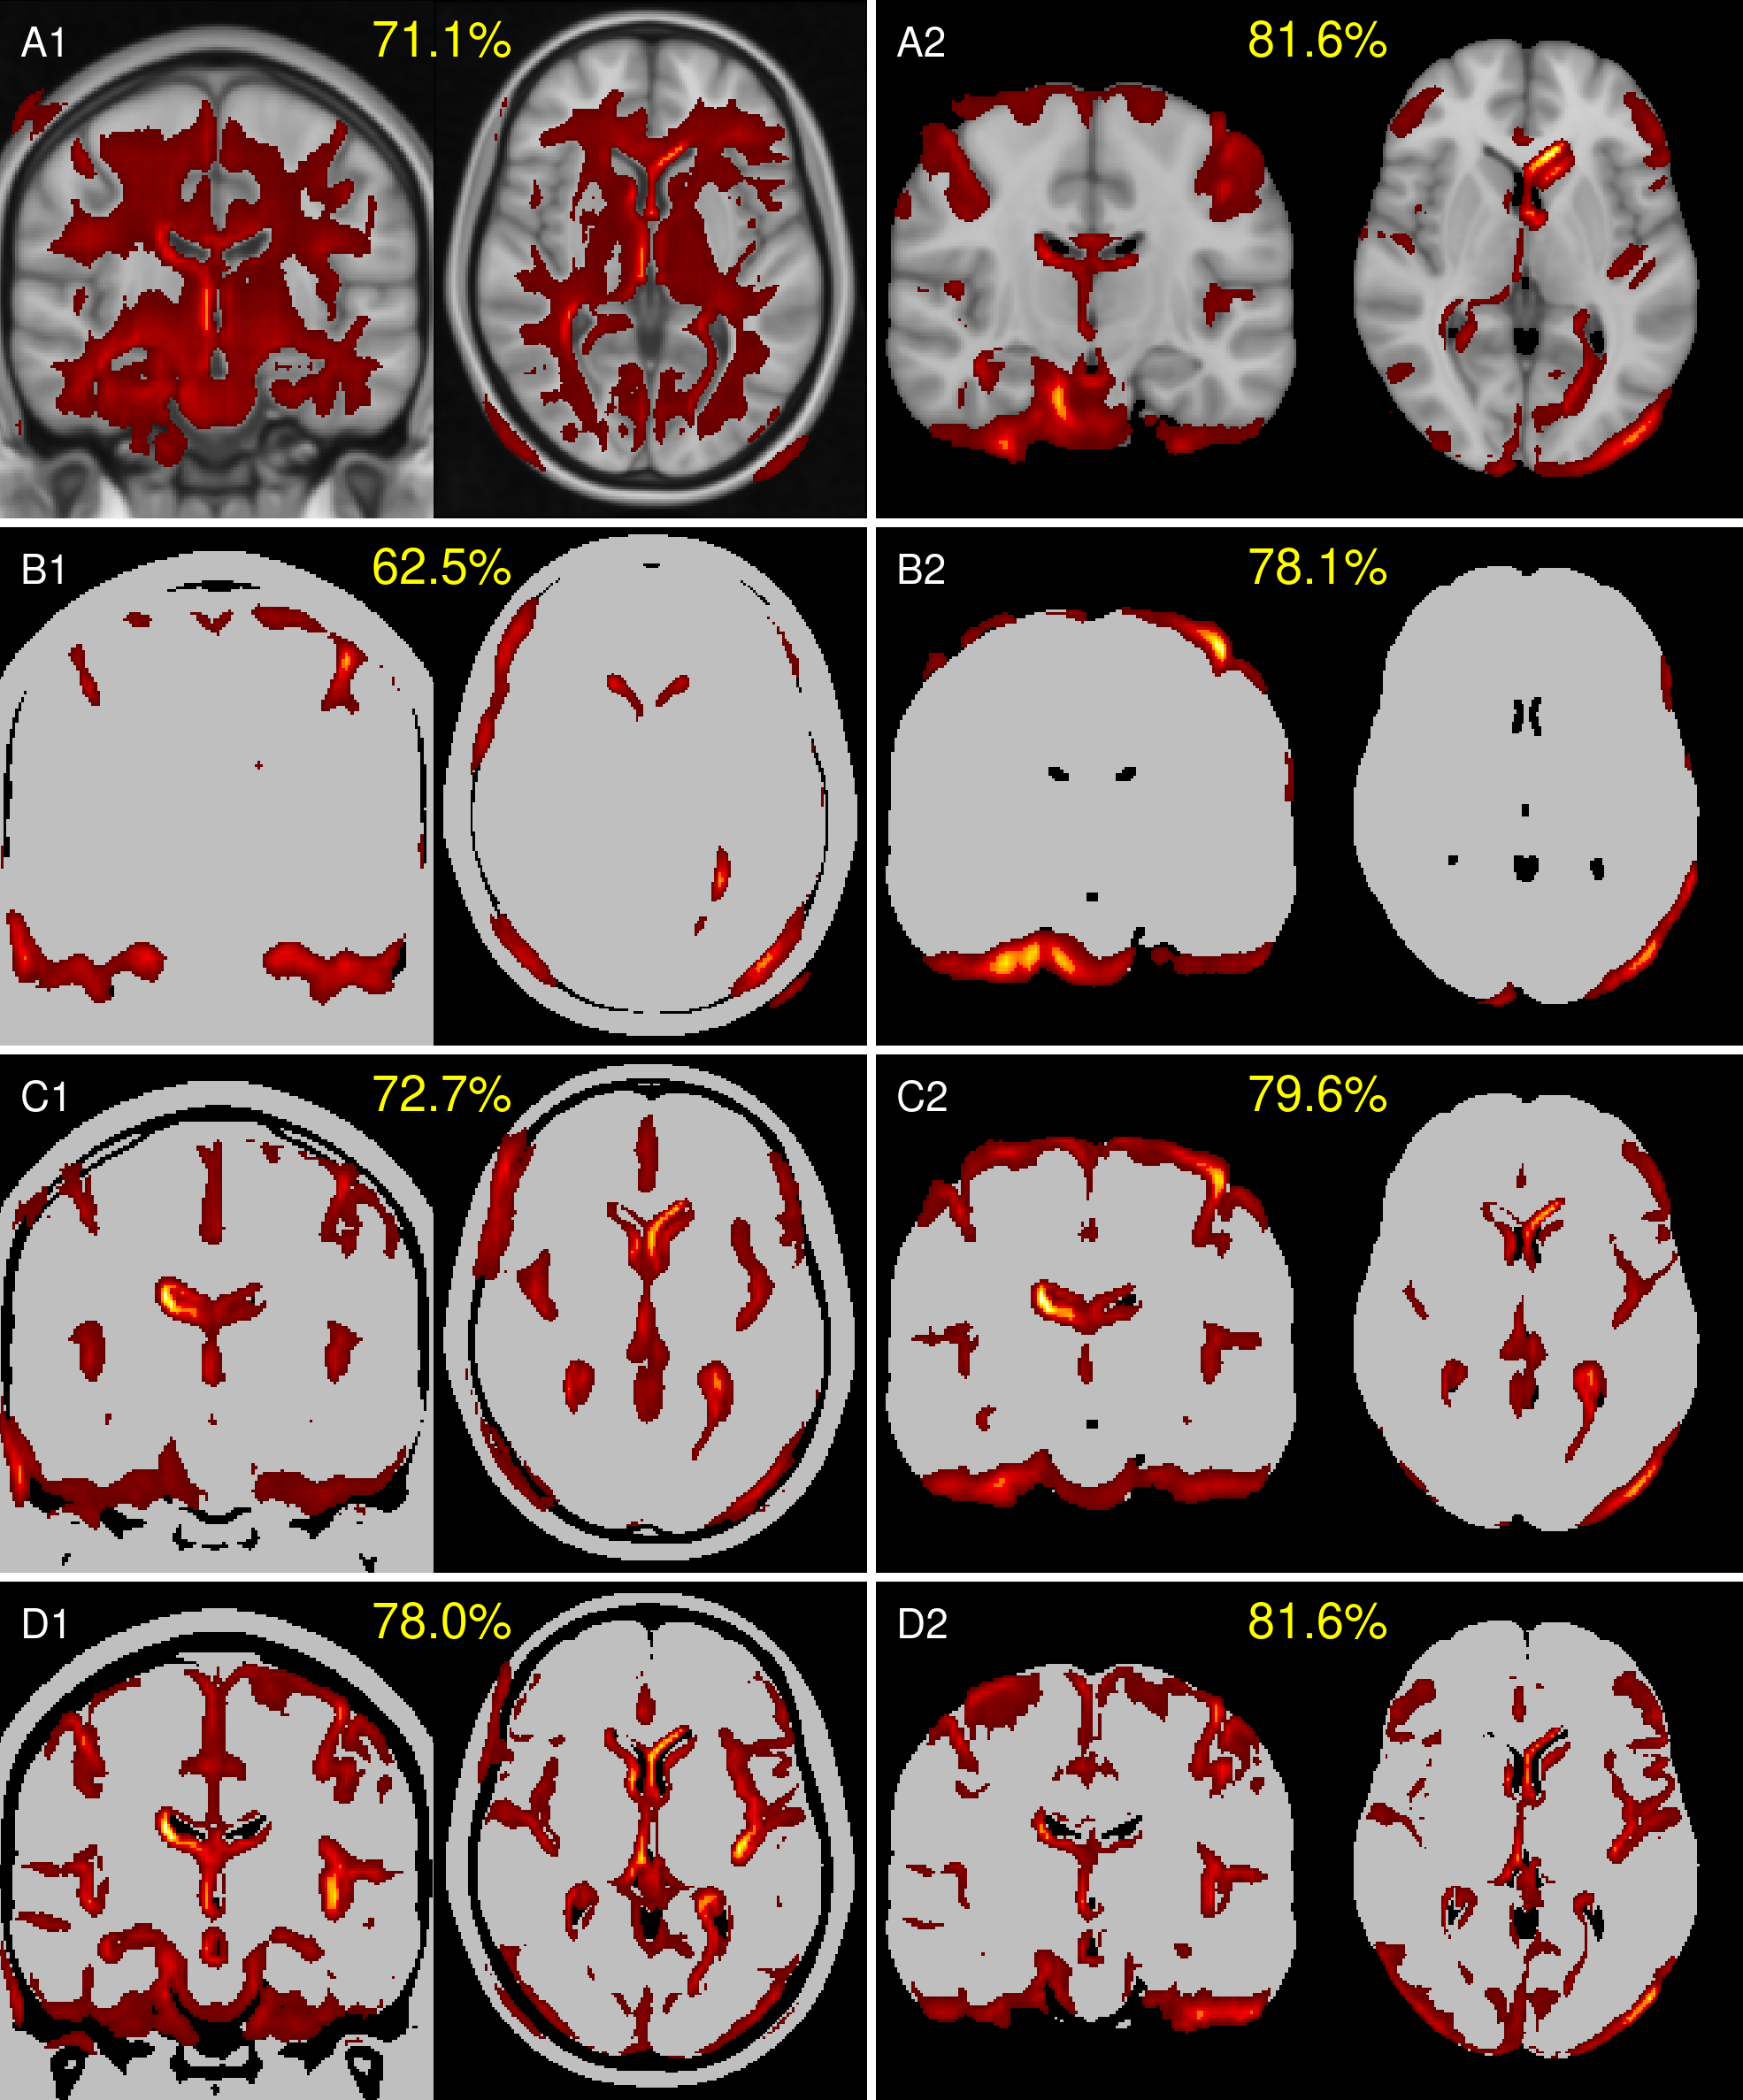

Figure 3 shows mean heatmaps for classification decisions on test images. Skull-stripping enhances classification accuracy, while mean heatmaps from binarized inputs closely resemble those from non-binarized inputs.

Heatmaps from the skull-stripped model (A2) serve as the reference for structural heatmap comparisons in Table 3. Skull-stripped binarization (B2, C2, D2) shows lower voxel-wise dissimilarity (RMSE), higher global similarity (Pearson Correlation), and improved localized similarity (MSSIM, EMD) compared to the aligned versions (A1, B1, C1, D1). Among the binarized models, skull-stripped-binarization-13.75% (B2) demonstrates the highest overall structural similarity (RMSE, Pearson Correlation, MSSIM, EMD) with the reference (A2), while skull-stripped-binarization-27.50% exhibits the strongest regional overlap with the reference. These results emphasize the dominant role of volumetric features over T1w contrast variations. Features similarities and model misclassification analysis were furthermore done using spectral clustering [24, 27] and t-distributed stochastic neighbor embedding [28]. See Supplementary Material 5 for an introduction and results.

Refer to caption

Figure 3: Mean heatmaps from test images: Left column with (A1) aligned T1w MRI, identical binarized T1w image with threshold levels (B1) 13.75%, (C1) 27.50% (C1) and (D1) 41.25%, and right column with corresponding skull-stripped versions (A2, B2, C2, D2). The mean accuracies of the models are shown in yellow.

We investigated three binarization levels, each aligned with the white matter intensity peak of the image, as depicted in Figure 1. These levels, although chosen arbitrarily, retained differing proportions of anatomical structures, capturing distinct aspects of atrophy, including ventricular enlargement, hippocampal shrinking and cerebellum morphology. As CNNs seem to focus on high-contrast regions [15, 31], these binarization levels allowed us to systematically dissect how different volumetric and structural features influenced model predictions.

Performance metrics, summarized in Table 2, reveal that removing gray-white matter contrast while retaining skull-stripping has little to no effect on model performance. Statistical analyses using exact McNemar tests, adjusted with discrete Bonferroni-Holm correction (α=.05\alpha=.05), revealed minimal evidence of significant differences in accuracy, sensitivity, and specificity across configurations when compared to the reference model. Specifically, skull-stripped and binarized models at thresholds of 13.75%, 27.50%, and 41.25%, as well as aligned images binarized at 41.25%, showed fewer than 10% of comparisons with significant differences. This suggests that volumetric information is sufficient for achieving high classification accuracy in CNN-based AD classification, with minimal contribution from gray-white texture variations.

Given the consistent model performances across configurations, we examined structural image similarities using similarity metrics applied on heatmaps, shown in Table 3. Surprisingly, the model trained with binarization at 13.75% (B2) -which retains the most tissue within the brain mask- exhibited the highest similarity to the reference model (A2) across global (RMSE, Pearson correlation) and localized (MSSIM, EMD) similarity metrics. This indicates that the key volumetric and morphological features driving classification are predominantly encoded in the brain mask’s volume and shape.

Furthermore, starting at binarization-27.50% (C1, C2), models began to incorporate additional regions such as the ventricles, with binarization at 41.25% (D1, D2) capturing also hippocampal features. Notably, the highest overlaps between reference and binarized models were observed at 27.50% (C2), as indicated by intersection-over-union metrics. This suggests that contrast in ventricular regions in the reference model provides sufficient signal for the model to identify disease-relevant patterns.